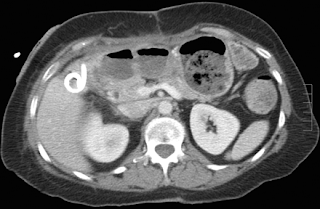

Images in a 66-year-old woman with a right upper quadrant abscess that occurred after cholecystectomy. (a) Transverse contrast-enhanced supine CT image shows abscess (arrow) in the gallbladder fossa. (b) Sagittal US image of the abscess obtained immediately prior to US-guided drainage shows multiple septations (arrow). (c) Transverse contrast-enhanced supine CT image shows residual abscess collection (arrow) identified next to the drainage catheter. (d) Transverse contrast-enhanced supine CT image obtained following intracavitary administration of 4 mg of tPA in 50 mL of 0.9% saline twice daily for 3 days shows no residual collection. The catheter was then removed, and there was no recurrence of the abscess cavity.